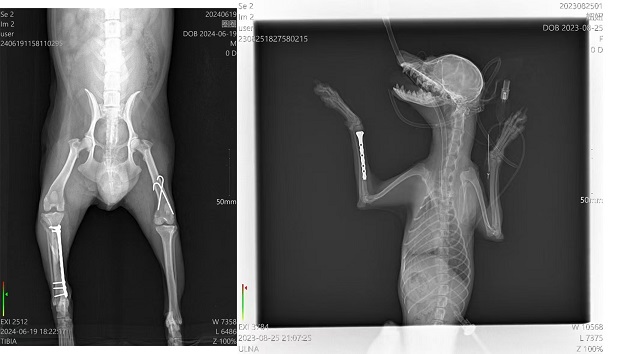

11月6日零基础骨科班现报名人数已满,感谢学员们的信任与选择。已超出本期报名名额的学员安排在本年度12月底一期。本班课程为5天,学员从骨解剖、麻醉、手术通路、骨折骨板、缝合、术后X片及用药全部为实体操作。无围观、无PPT,全天侯手把手教学操作,学后确保独立完成骨科手术。